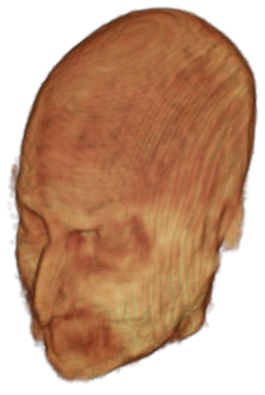

The digitalization of heath records has increased the risk of –and impact of– large scale data leaks. Although data compliance standards have been enacted to protect health records (HIPAA and GDPR), privacy of medical data is a growing concern. Three-dimensional scans such as magnetic resonance images (MRI) and computed tomography (CT), for example, contain an intrinsic privacy risk [Lotan et al.(2020)Lotan, Tschider, Sodickson, Caplan, Bruno, Zhang, and Lui]. Detailed renderings of the head can be crafted from 3D scans using techniques such as volumetric raycasting, as in Figure 1. This vulnerability can expose the patient’s identity if the renderings are matched to a face database [Mazura et al.(2012)Mazura, Juluru, Chen, Morgan, John, and Siegel, Lotan et al.(2020)Lotan, Tschider, Sodickson, Caplan, Bruno, Zhang, and Lui].

Therefore, in this work, we define a new class of de-identification techniques that remodels the privacy-sensitive regions without altering the content of medically relevant data (see Figure 1). Under such a remodeling approach, the face, eyes, oral and nasal cavities, etc. should exhibit realistic appearance and structure of appropriate size, but should otherwise be independent of the original data. To solve this task, we propose a novel model called Convex Privacy GAN, or CP-GAN, that conditions on a convex hull of the skull extracted from the scan to be de-identified. The generator learns to synthesize volumes that preserve medically-sensitive regions such as the brain, while non-invertibly remodeling privacy-sensitive characteristics from the original scan.